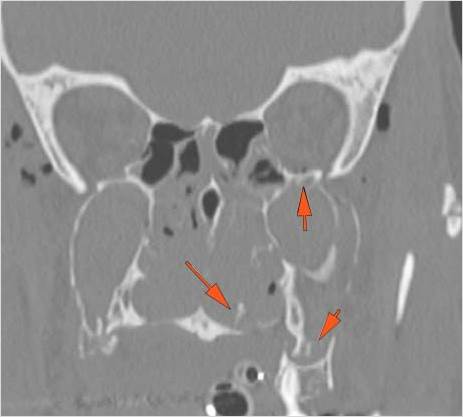

The medial, lateral and posterior maxillary walls are fractured.

The infraorbital rims and orbital process of the zygoma and/or frontozygomatic suture are fractured.

The alveolar ridge, premaxilla, and/or the palatine process of the maxillary bones on either side are fractured.

The the zygomatic arch, frontozygomatic suture or infraorbital rim are fractured.

The lateral wall of the orbit is fractured.